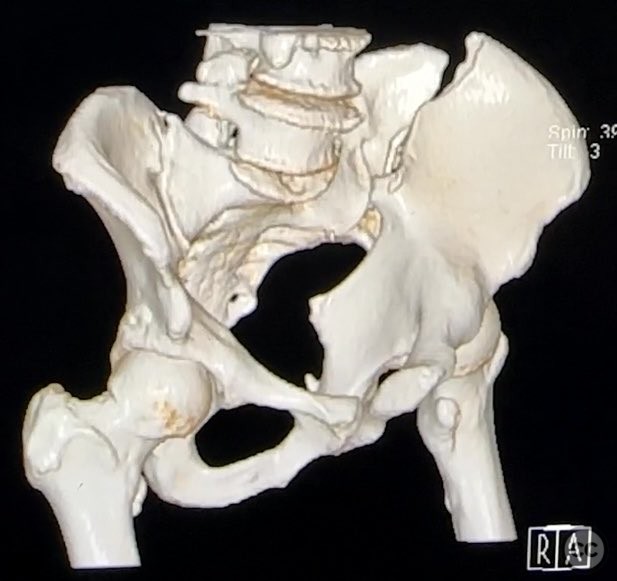

Complete Iliac Fracture with Symphysis Pubis Disruption and Contralateral Incomplete SI/Iliac Fracture

Clinical Details

Clinical and radiological findings:  A patient sustained a high-energy pelvic ring injury characterized by a complete left iliac fracture extending from the iliac crest to the greater sciatic notch, associated with a complete disruption of the symphysis pubis (SP). Additionally, there was a less displaced, incomplete right sacroiliac (SI)/iliac fracture. The injury pattern is consistent with an AO/OTA 61-B2.3 (lateral compression type II) pelvic ring injury. No neurovascular compromise or significant soft tissue injury was reported.

Patient positioning:  The patient was positioned supine with a sacral bump to facilitate reduction, and left-sided longitudinal traction was applied to aid in fracture alignment.

Anatomical surgical approach:  The surgical approach involved a direct anterior midline exposure to the symphysis pubis, followed by subperiosteal dissection to expose the disrupted SP. The ilioinguinal approach was utilized for the iliac fracture, with careful elevation of the abdominal musculature from the iliac crest and pelvic brim. The iliac fracture was reduced using a Farabeuf clamp at the linea terminalis (brim) and a tenaculum at the crista iliaca. The symphysis pubis was reduced with a tenaculum clamp.